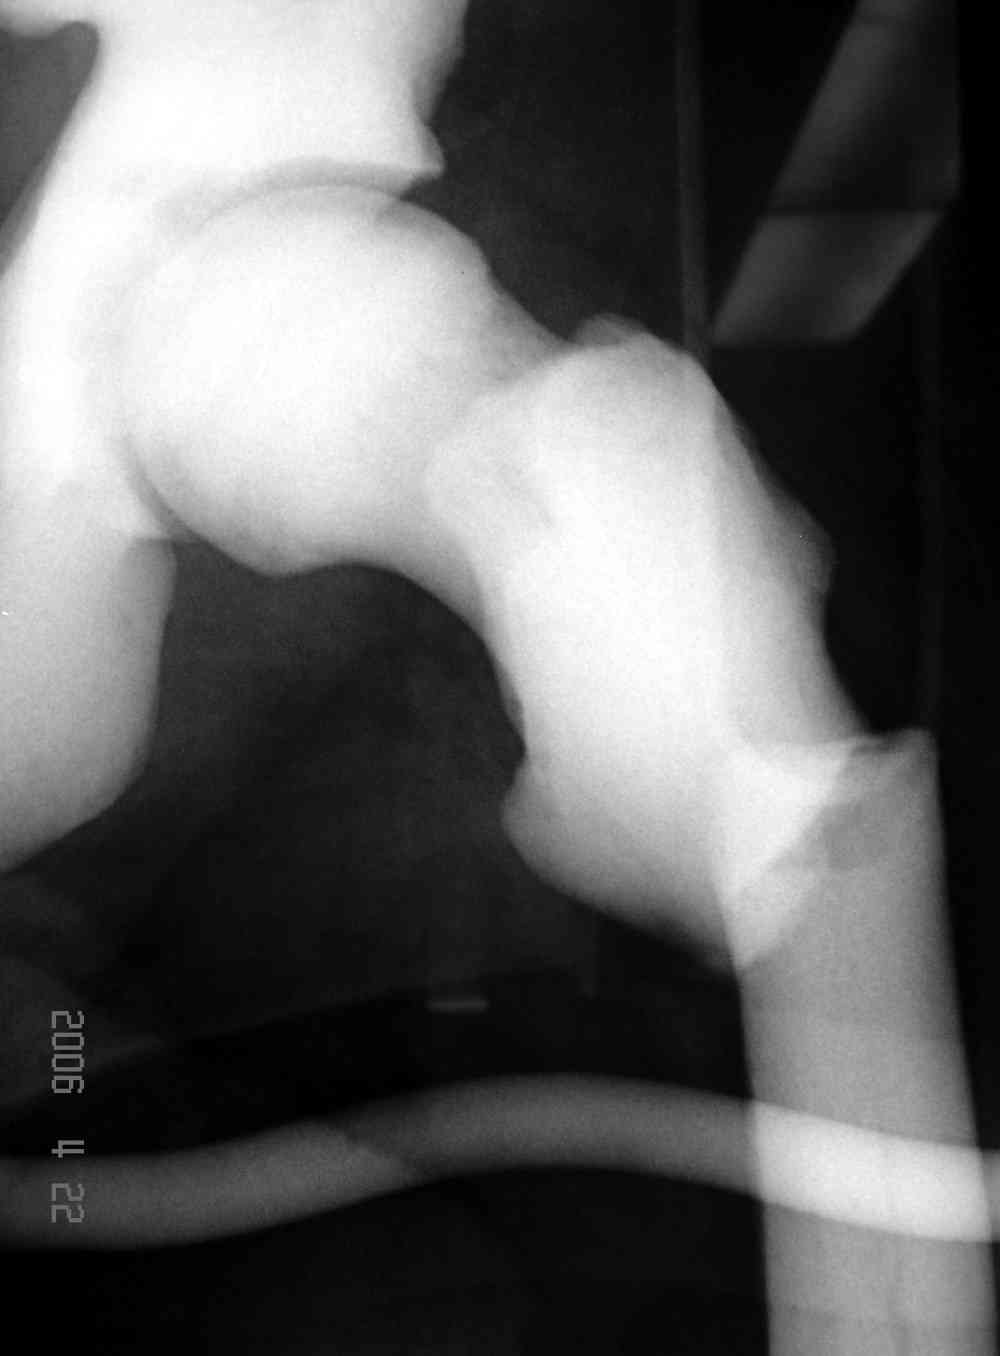

Не являюсь специалистом по костной патологии, но мне кажется, на ренгенограмме множественные мета-диафизарные образования напоминяющее змееподобных извилистых линии и периостеальные ламинирование очень напоминяет картину остеонекроза (инфаркта) костей, возможно связано с длительным применением стероидов.

При предоставлении дополнительных информации, сканнирования, МРТ и лабараторных данных можно уточнить предварительный диагноз, пока склонен к обширному костному инфаркту, и таких больных рекомендуем лечить сиптоматически.

слайды из прошлегодного случая.